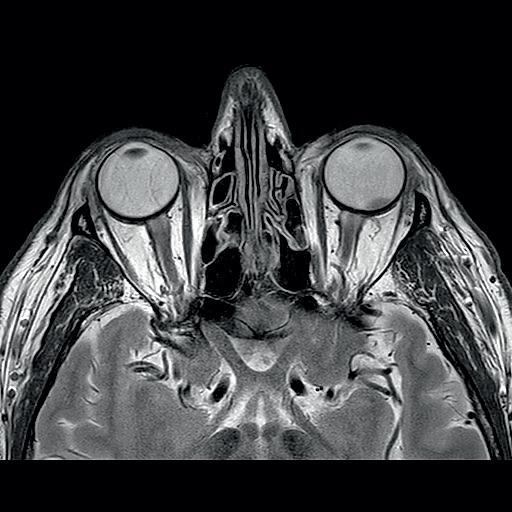

venstre øye høyre øye chiasma opticum n. opticus tractus opticus corpus geniculatum laterale area striata radiatio optica Figur 2.18 Synsbanen. Figur 2.19 Computertomografi (Ct) av øyehulene med synsnervene.

Figur 2.20A magnetisk resonanstomografi (mR) av øyehulene og hjernen. Figur 2.20B mR viser synsnervene, chiasma opticum og overgang til tractus opticus.